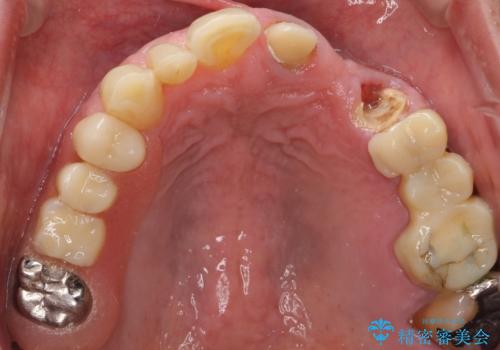

- ブリッジの支台歯であった左上の犬歯が折れたことを主訴に来院された患者様です。

犬歯は歯ぐきの奥深くまで割れており保存不可能な状態でしたが、どうしても抜きたくないとのことでした。

歯を牽引し健全歯質を歯肉縁上まで引き上げ、歯の保存を試みることにしました。